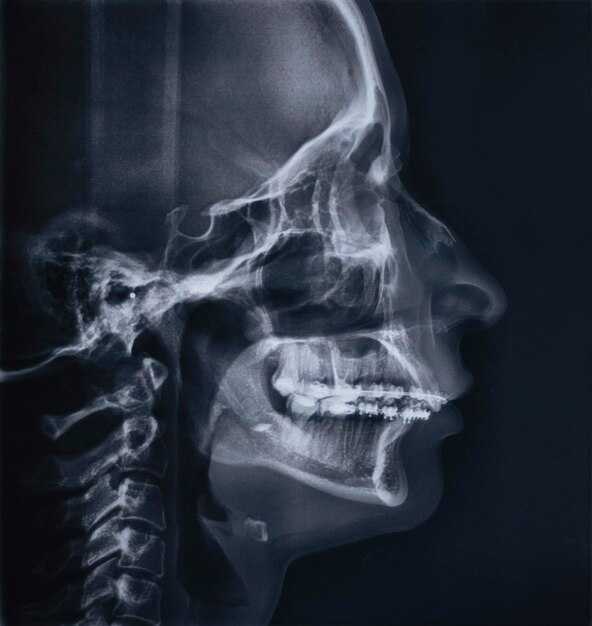

Сравнение обычного и панорамного рентгена при гайморите

Обычное и панорамное обследование предоставляют различную информацию о воспалении верхнечелюстной пазухи. При использовании традиционного метода рентгенографии изображение позволяет визуализировать состояние само?й пазухи, выявляя её заполнение, утолщение слизистой оболочки и возможные кисты.

Панорамный снимок охватывает более обширную зону, включая обе челюсти и верхние дыхательные пути. Это даёт возможность оценить влияние воспалительного процесса на соседние структуры, такие как зубы и другие пазухи. Специалисты часто рекомендуют панорамное обследование для оценки распространенности недуга и исключения сопутствующих заболеваний.

Важно отметить, что даже при высоком качестве панорамного изображения, местные изменения могут быть менее выраженными по сравнению с обычным методом, что иногда затрудняет диагностику. Однако панорамный вариант позволяет получить полное представление о состоянии челюстно-лицевой области.

Выбор между двумя подходами зависит от клинической ситуации и целей консультации. В некоторых случаях возможно использование сочетания методов для получения наиболее полной картины и принятия оптимального решения о лечении.